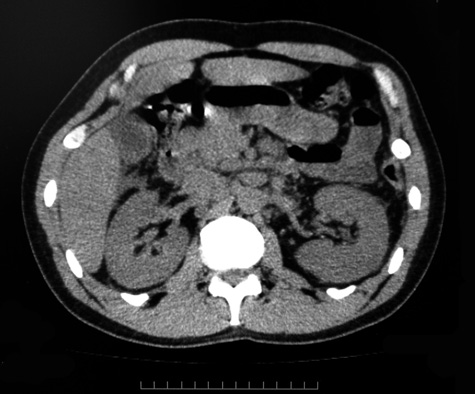

初診時CTでは肝門部にわずかなリンパ節腫大を認めたが, 不明熱発現12日後のCTでは、右肺底部浸潤影, 肝脾腫大にくわえて胃周囲, 肝鎌状靱帯, 傍大動脈領域リンパ節が多数腫大していた。診断確定のため開腹リンパ節生検を計画したが全身状態が急激に悪化, MOF状態に陥いる。生検をあきらめ臨床,画像診断より悪性リンパ腫と診断, CHOP like therapyを1コース施行した。治療は著効し解熱, MOF状態は改善した。全身状態改善後肝針生検を行うが異常細胞は認められなかった。CHOP-like療法/3週間を3コース終了。中枢神経再発の予防に髄液検査とMDA療法の髄注を追加した。sIL-2 27700→424と正常化, CTでCRの効果確認され退院。以後外来で追加化学療法を施行した。